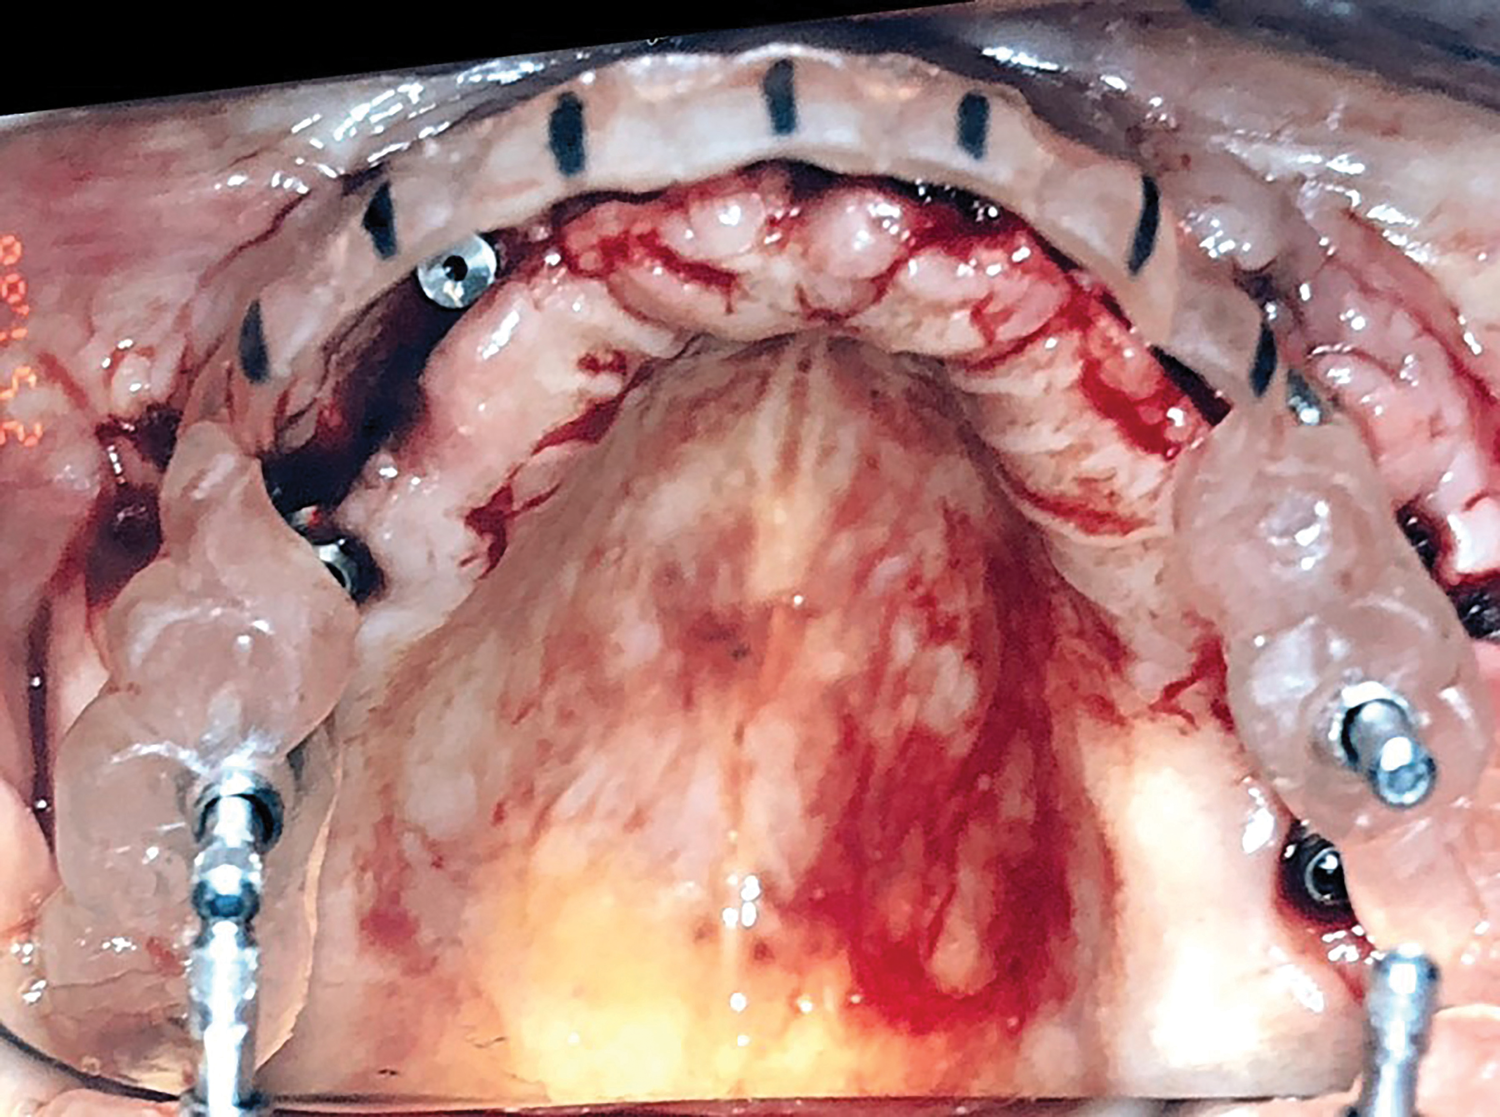

Fig 10. Occlusal view showing use of surgical guide for implant placement.

Figure 10

Three weeks later (Figure 8), an impression was taken (Figure 9) for a laboratory-processed, screw-retained, implant-supported provisional prosthesis. Six months later, the TIs on sites Nos. 5, 8, 9, and 12 were removed, and two implants (Biomet 3i, 3.25 mm x 13 mm) were placed in sites Nos. 8 and 10 using a surgical guide. Cover screws were then placed (Figure 10). The fixed laboratory-fabricated provisional prosthesis was screwed in on implants Nos. 2, 3, 4, 13, and 14 (Figure 11). After 4 months, the patient presented with uneventful healing, and second-stage surgery was performed on implants Nos. 6, 8, 10, and 11 (Figure 12).